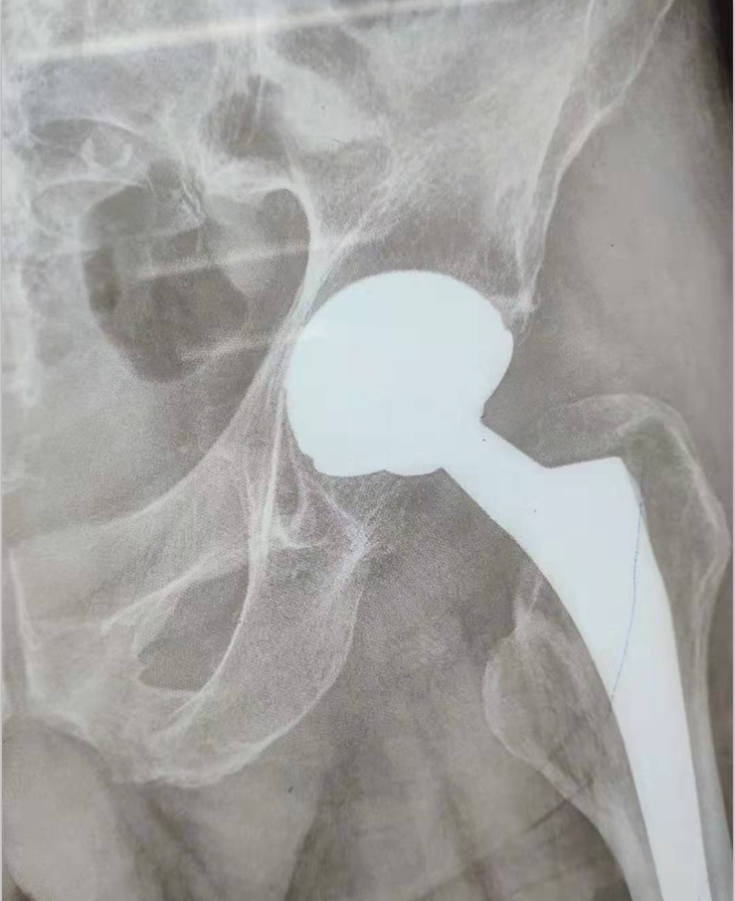

手术非常顺利,术后1天,患者就可以下床尝试进行康复活动了,短短几天,原来的髋关节疼痛消失,术前活动受限的关节也随之恢复,患者和家属都非常感谢张主任团队为他进行此项手术,不仅为他解除了病痛,还让他可以继续进行左侧肢体的复健训练。

患者术后影像学资料